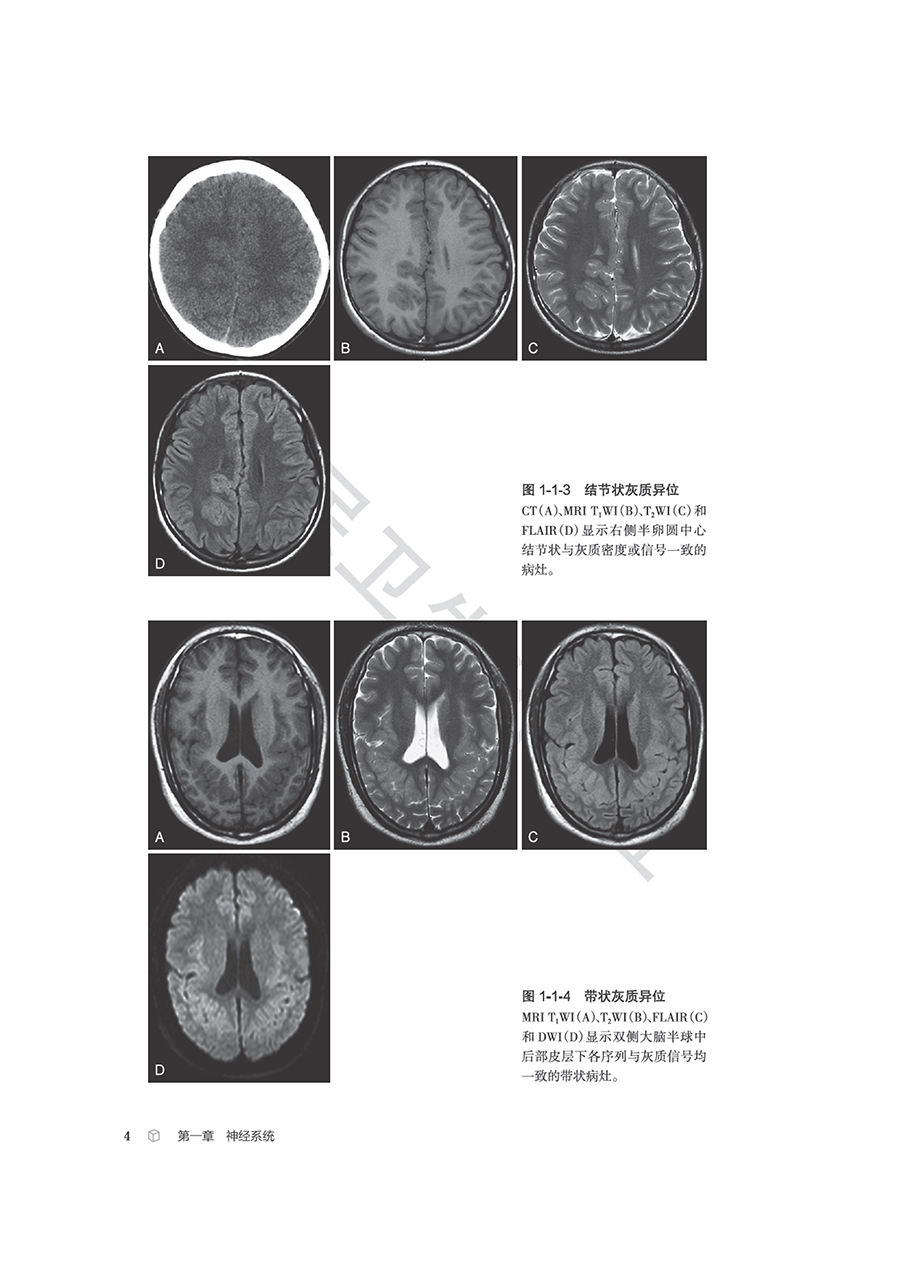

本书从影像科医师的日常工作出发,以中华医学会放射学分会青年学组的“青影智慧-影像诊断思维系列培训课程”内容为基础,系统梳理、收录神经系统、头颈与五官、呼吸系统、心脏和大血管、乳腺、消化系统、泌尿系统、生殖系统、骨关节等影像科日常工作中的近300个常见征象,从每个征象的分析入手,凝练影像征象的特征,辅以征象典型图进行说明,应用思维导图展现征象分析和诊断的思路,并融入鉴别诊断点和相应的疾病谱,抽丝剥茧,去伪存真,示范从影像征象到诊断疾病的思维过程。